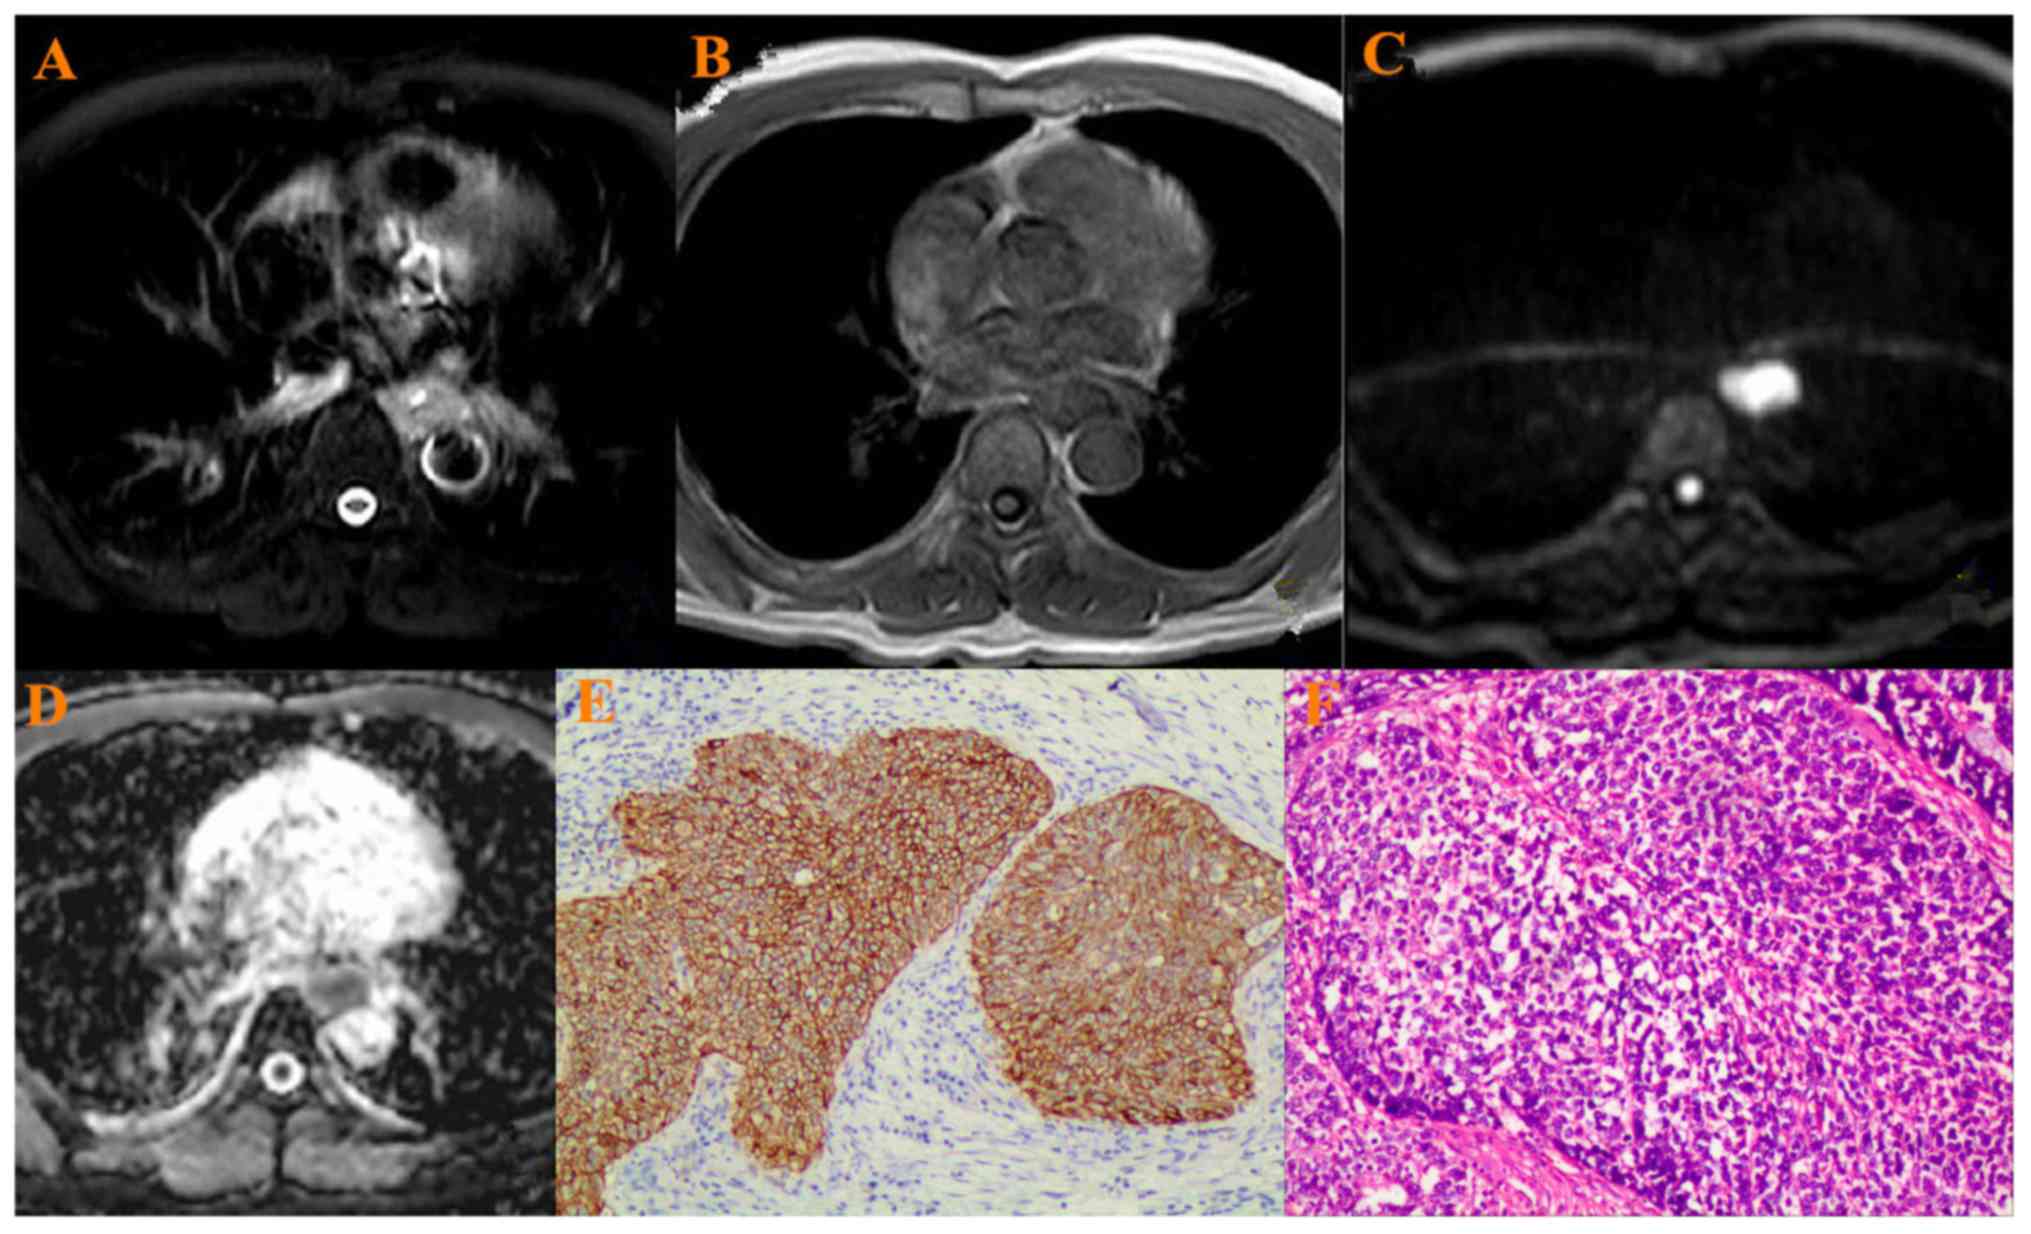

Figure 3.

A 72-year-old patient with ESCC in the mid-thoracic portion. (A) ESCC was hyperintense on T2-weighted image, (B) hypointense on T1-weighted image, (C) hyperintense on the DW-MRI (b=800 s/mm2) (D) hypointense on ADC map. ADC value: 1.31±0.25×10−3 mm2/s. (E) High VEGF staining in cytoplasm of ESCC: Strong positive (+++) (×200 magnification), (F) Histopathology: Poorly differentiated squamous cell carcinoma (×200 magnification). ESCC, esophageal squamous cell carcinoma; DW-MRI, diffusion weighted-magnetic resonance imaging; ADC, apparent diffusion coefficient; VEGF, vascular endothelial growth factor.